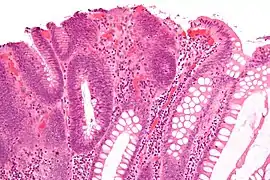

| Tubulovillous adenoma | 20% to 25%[15] | 25–75% villous[14] | ![]() | |

| Villous adenoma | 15%[16] to 40%[15] | Over 75% villous[14] | ![]() | |

The villous subdivision is associated with the highest malignant potential because they generally have the largest surface area. (This is because the villi are projections into the lumen and hence have a bigger surface area.) However, villous adenomas are no more likely than tubular or tubulovillous adenomas to become cancerous if their sizes are all the same.[18]

Micrograph of a villous adenoma. These polyps are considered to have a high risk of malignant transformation. H&E stain.